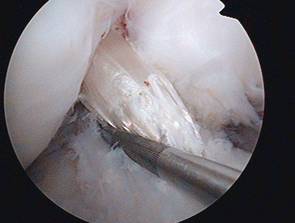

Der arthroskopische Ersatz des vorderen Kreuzbandes (Kreuzbandplastik) ist heute Standard. Als Bandersatz dienen körpereigene Transplantate. Ich verwende dazu die Semitendinosus-/Gracilis Sehnen, die über eine Mini –Inzision entnommen werden können und deren Reißfestigkeit höher als die des ursprünglichen Bandes ist.. Der Vorteil dieses Transplantates ist ein Ausbleiben des vorderen Kniegelenkschmerzes (früher häufig bei Patellasehnenplastiken).

Kreuzbandersatzplastik